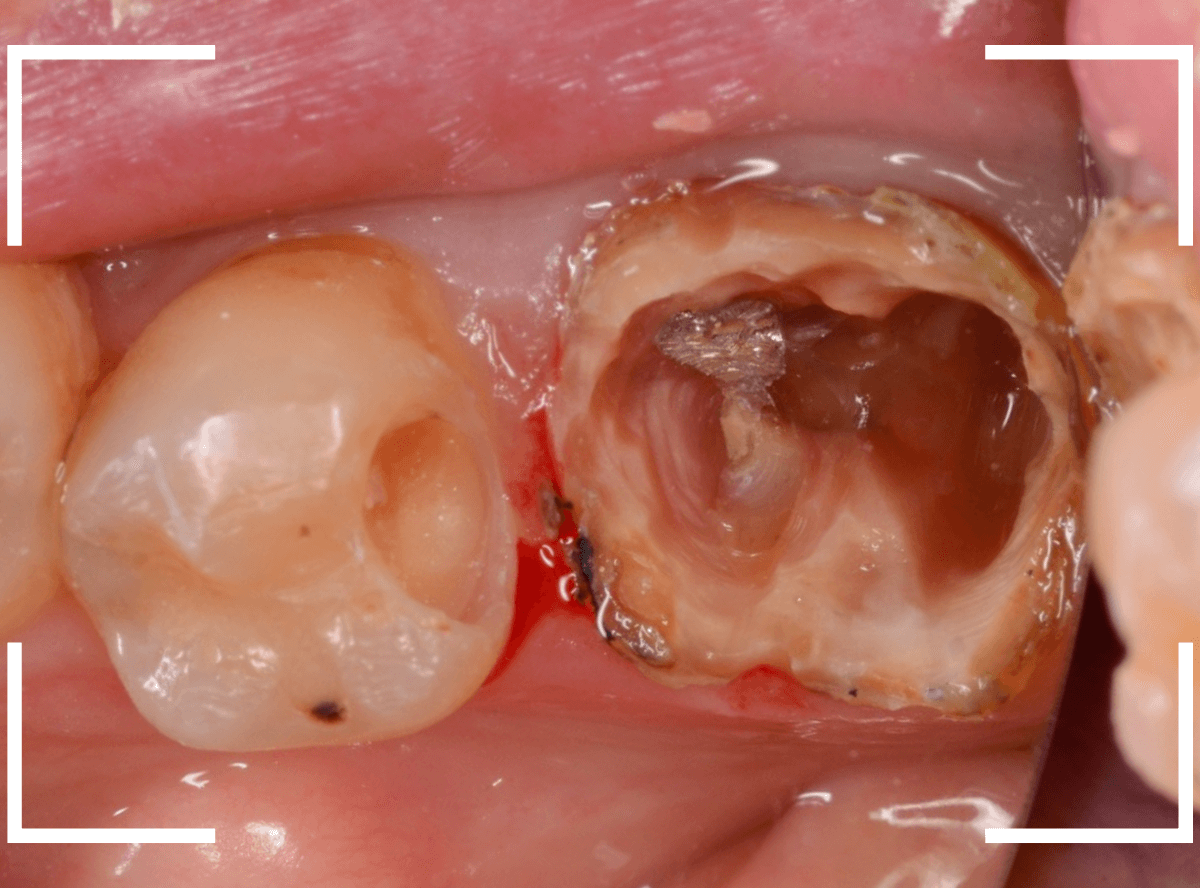

今回は、深い虫歯が進行してしまったさし歯をセラミックで治療し直したケースを動画でご紹介します。

検査をすると、さし歯の周りの歯肉から出血が多いため、レントゲン写真で確認すると、さし歯の中で虫歯が進行していると診断されました。

神経を取っているさし歯の中の虫歯は、レントゲン写真でも正確にはわからず痛みもないため、さし歯をはずしてみないと、どれくらい進行しているかははっきりわかりません。

虫歯と診断されたさし歯の中は一体どうなっているのでしょうか?